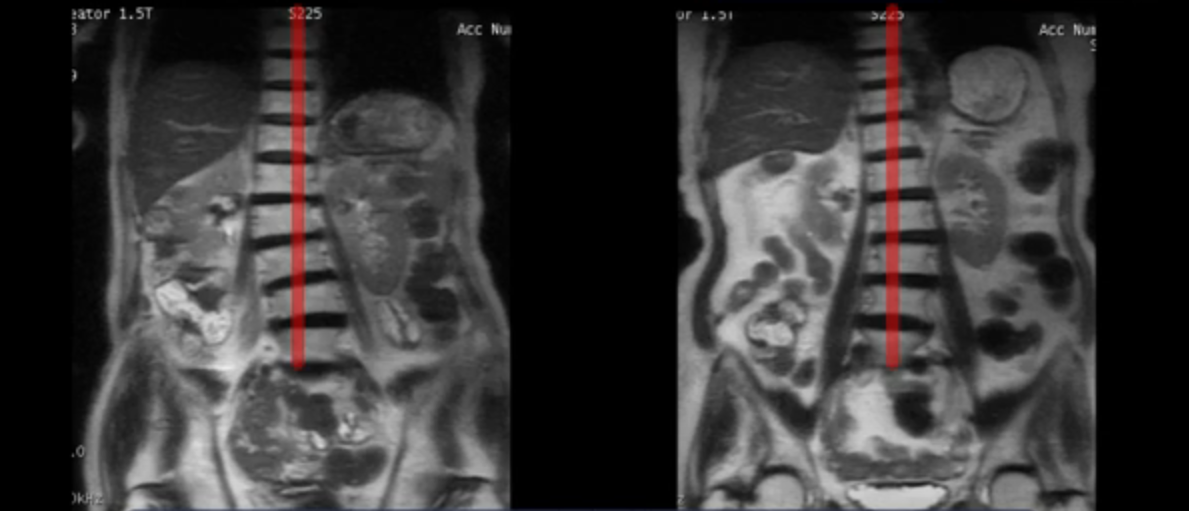

이 환자분들 척추가 삐뚤어진 게 보이실 겁니다. 심하게 틀어진 사람을 골라서 보여주는 게 아니라 70대 이후의 모든 협착증 환자는 전부 다 이렇게 허리가 틀어져있습니다. 허리가 틀어져있다는 얘기는 근육이 다 뒤틀려있다는 얘기입니다. 이렇게 근육의 상태가 안 좋아질수록 신경이 더 눌리니까 협착증 증상은 점점 더 심해집니다.